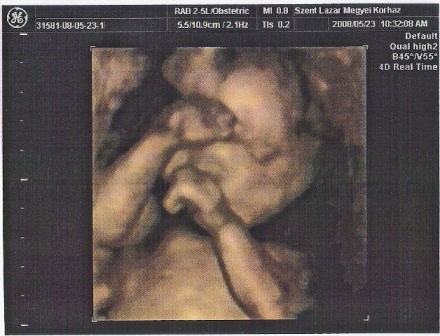

Petra, annyira jók ezek a képek! Hol csinálták?! Hihetetlenül jól látszik Hanna Róza!